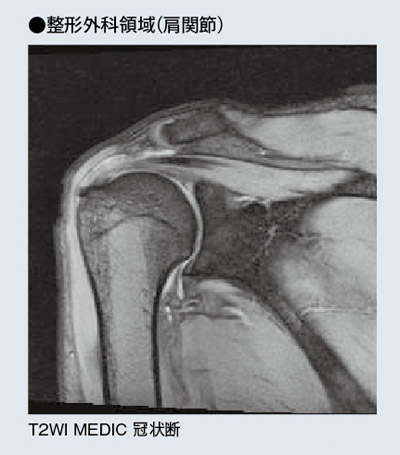

さらに,上野技師は,MAGNETOM ESSENZAだけにオプションで搭載可能な“Focus Shoulder Array coil”について,次のように評価している。

「Focus Shoulder Array coilは,コイルの中に設置したシムコイルに合わせてシミングをかけられますので,磁場中心にポジショニングすることが困難な肩の撮像でも,磁場均一性の高いきわめて明瞭な画像が得られます。ルーチン検査時間の中で,これほど高精細な画像を得られたのは初めてです」

Focus Shoulder Array coilにより,関心領域が磁場中心になくても良好なSNRが得られている。